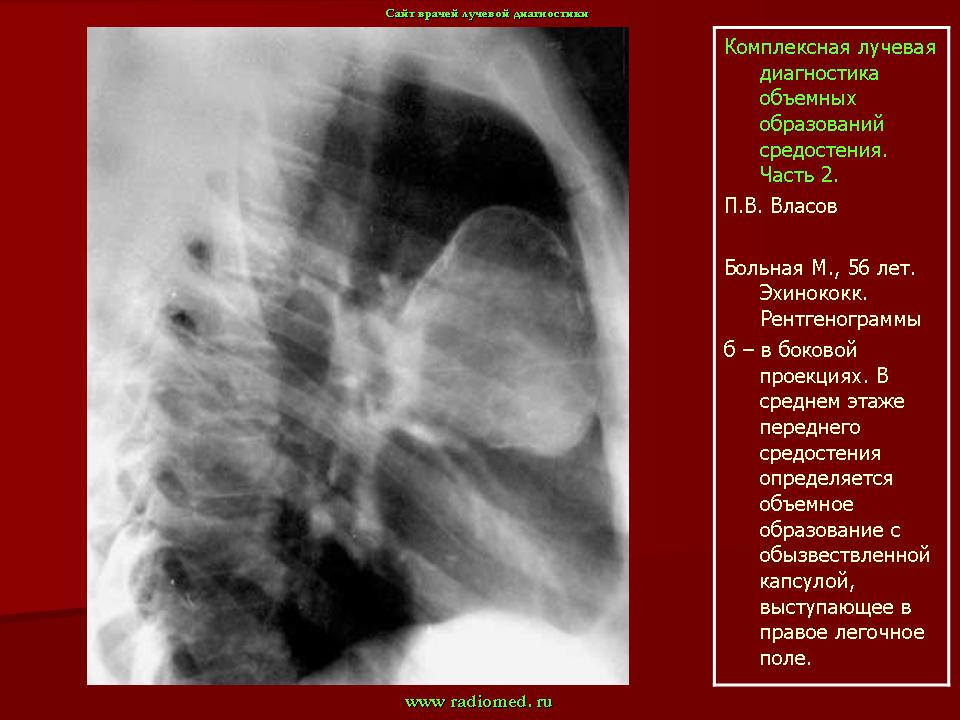

Разрушение тех или иных костей, особенно составляющих скелет грудной клетки, может иметь при эхинококковой кисте и принципиально иной характер — эхинококк распространяется на костную ткань извне, со стороны мягких тканей, скажем, при эхинококке легкого больших размеров, растущего в сторону ребер. Но ведь это уже не первичный эхинококк костей и здесь вступают в силу совершенно другие рентгенологические закономерности.